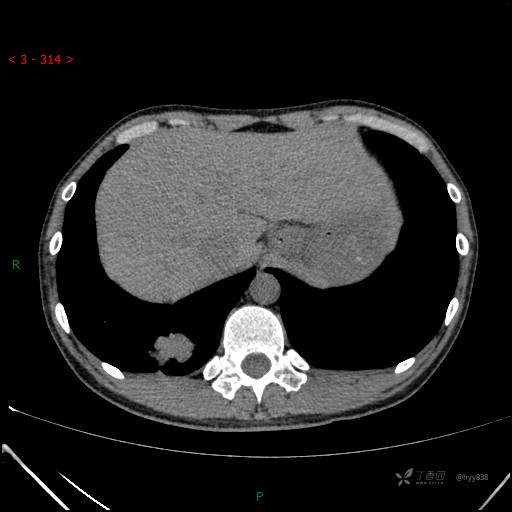

胸部CT平扫